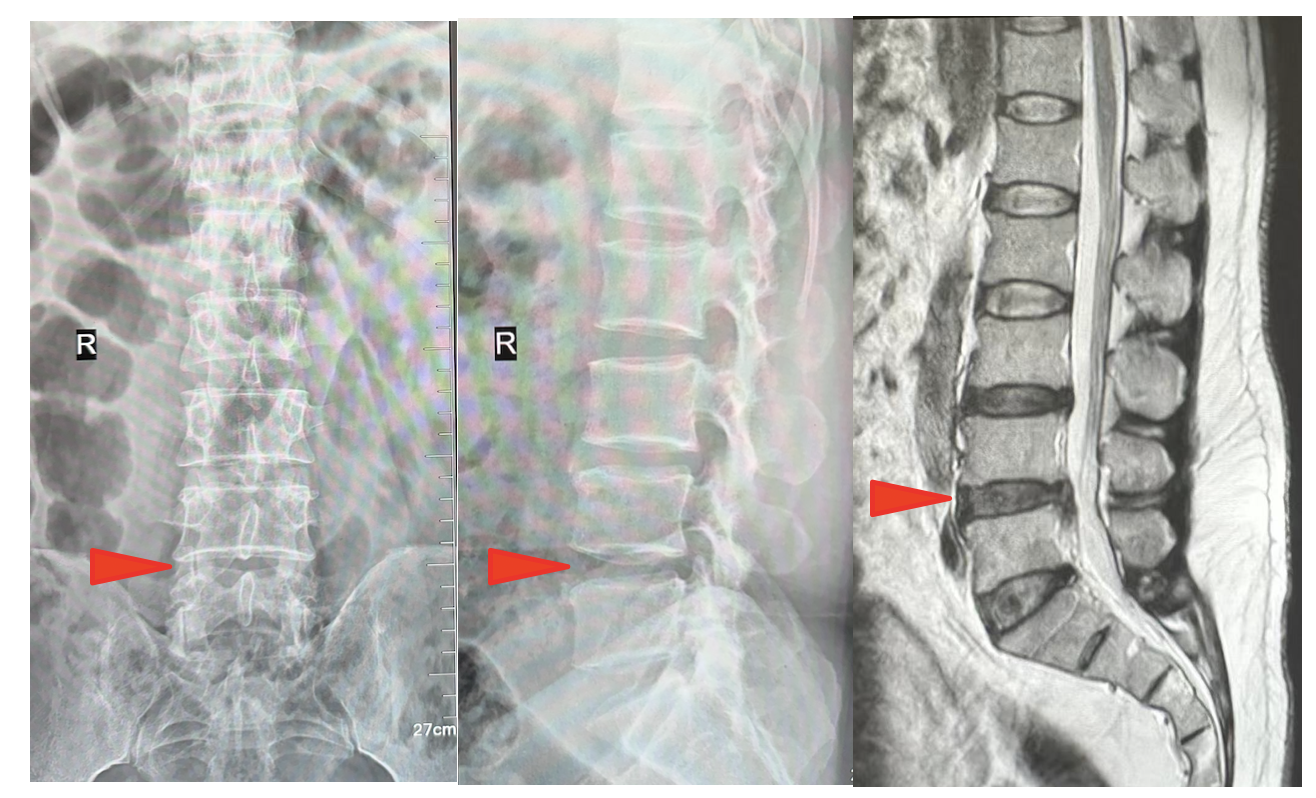

姬传磊进行系统检查评估后,诊断为腰椎间盘突出症。鉴于保守治疗效果不佳,且患者正值壮年、劳动需求大,手术治疗为理想选择。但传统开放手术创伤大、恢复慢,经充分评估和综合考量,与患者家属充分沟通并取得同意后,决定在全麻下行椎间孔镜下腰4-5椎间盘摘除、椎管减压术。该手术属四级手术,技术要求高、操作难度大,对骨科团队提出了不小的挑战。

经过充分术前准备,姬传磊主任团队凭借娴熟的技术,通过两个1cm微小切口精准摘除突出髓核,手术顺利结束。次日,患者症状改善,下肢疼痛、酸胀、麻木感逐渐消失,肢体活动自如。1周后,患者恢复良好,疼痛症状显著缓解,对疗效表示满意并顺利出院。